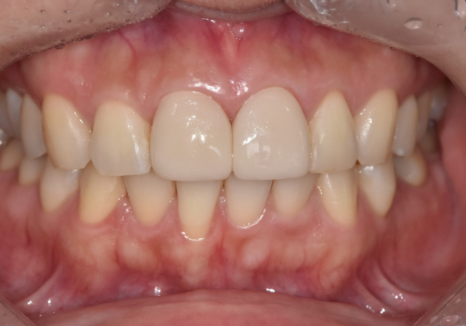

앞니 레진 파절과 변색을 해결한 라미네이트 치료 과정

강일역 치과, 검게 보이는 앞니 레진 변색, 무조건 새로 해야 할까요?

성형을 생각하실 때도

예뻐졌다는 말은 듣고 싶은데

성형 한 티 나는 건 싫다는 말씀,

많이 하시잖아요.

앞니 라미네이트도

딱 그 느낌입니다.

그래서 이번 치료에서도

"딱 봐도 라미네이트네."가 아니라,

원래 내 치아였던 것처럼 보이되,

밝고 자연스러운 느낌을

가장 중요한 기준으로 잡았습니다.

앞니는 특히

색감, 투명도, 끝선 형태가

조금만 달라도

옆 치아랑 따로 노는 느낌이 바로 납니다.

저희 병원이

원내 기공소를 운영하는 이유도

바로 이 부분 때문입니다.

진료실에서 확인한 기준을

기공사와 바로 공유하고,

처음부터 방향을 맞춰 제작할 수 있습니다.

이번 케이스도

기공모델 단계에서부터 형태를 점검하고,

최종 보철물 역시

자연치아와 섞였을 때 어색하지 않도록

톤과 윤곽을 정리해 완성했습니다.

그 덕분에

재제작으로 시간을 끌기보다는

계획한 흐름대로

부착까지 자연스럽게 이어갈 수 있었습니다.

251201(전) 251206 (후)